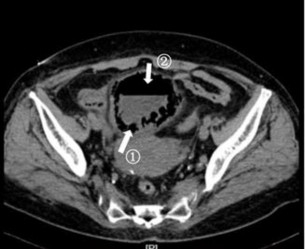

Management and outcome

Of the 13 patients in our study, 12 were managed with medical therapy, including glycemic control, urine drainage, and antibiotic administration. Only one patient underwent partial cystectomy because of ineffective conservative treatment. All the patients recovered and no death was recorded (Figure 2).

Figure 2: Computed tomography reveals gas has nearly disappeared after treatment